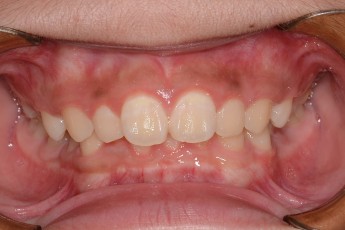

Before

After